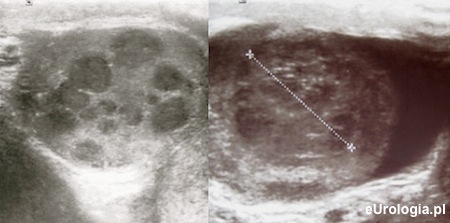

Najczęściej zgłaszanym przez pacjentów objawem jest niebolesne powiększenie jądra lub zmiana jego konsystencji - jądro staje się twarde. Jeśli lekarz podejrzewa nowotwór jdra konieczne jest wykonanie USG moszny i oznaczenie markerów nowotworowych. USG moszny jest nieinwazyjnym badaniem o wysokiej swoistości i z reguły jest wystarczające do podjęcia decyzji o leczeniu operacyjnym. Markery nowotworowe w przypadku podejrzenia raka jądra oznaczane są z surowicy krwi. Podstawowymi markerami raka jądra są AFP, Beta - HCG i LDH.

Fot. Ultrasonograficzny obraz nowotworów jądra.